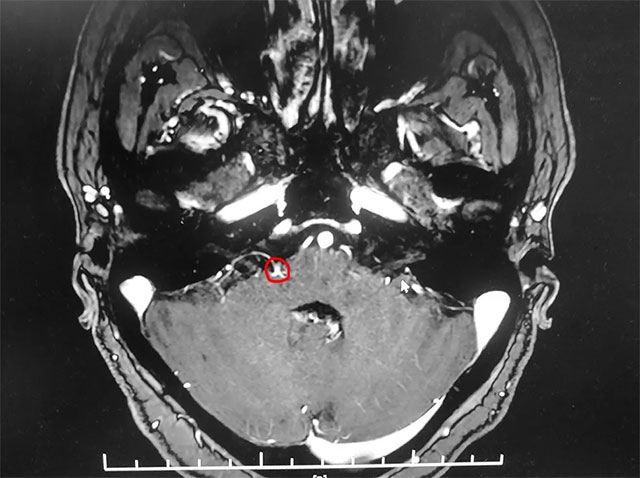

▲ 患者右側(cè)面神經(jīng)與周圍小血管關(guān)系密切

入院后,經(jīng)面神經(jīng)MRTA平掃+增強(qiáng)檢查顯示,患者右側(cè)面神經(jīng)與周圍小血管關(guān)系密切。在對患者病情及影像學(xué)資料進(jìn)行評估,并告知患者及家屬手術(shù)風(fēng)險后,上海藍(lán)十字腦科醫(yī)院神經(jīng)外科主任沈建康教授團(tuán)隊為患者實(shí)施了面神經(jīng)微血管減壓手術(shù)。